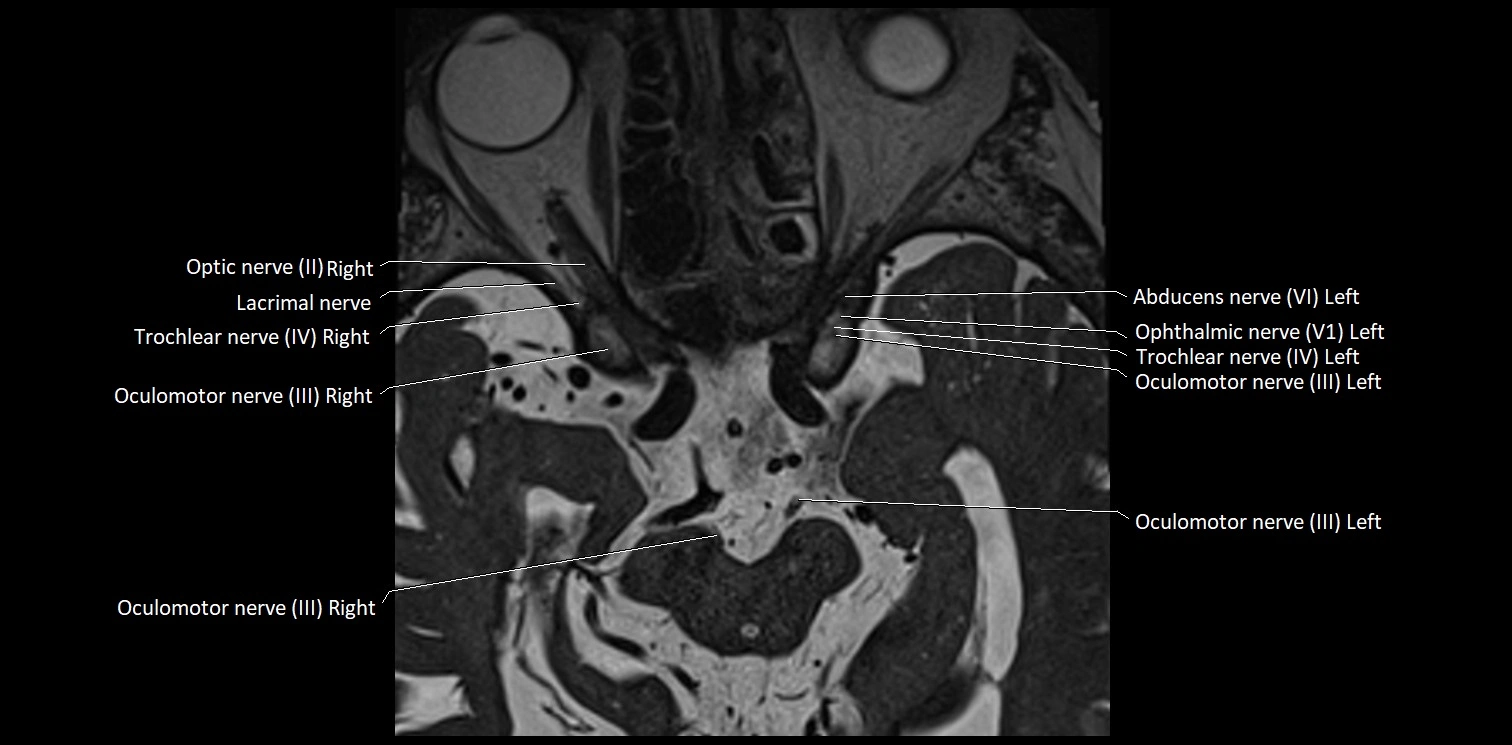

MRI Appearance

• The abducens nerve is a small, thin, linear structure

• Best visualized on high-resolution T2-weighted 3D MRI sequences (e.g., FIESTA or CISS)

• Seen as a hypointense (dark) line running from the brainstem at the pontomedullary junction, traversing the prepontine cistern, and entering Dorello’s canal under the petrosphenoidal ligament, then into the cavernous sinus, and finally the orbit

• May be challenging to visualize in standard MRI due to its small size

• Pathology may be inferred by absence, displacement, or enhancement of the nerve

MRI images

image